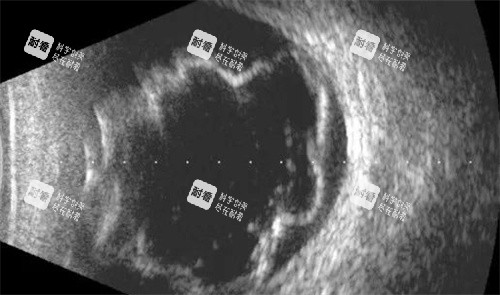

眼底病是眼科中较为复杂且严峻的一类疾病,如视网膜脱离、黄斑病变等,这些疾病不仅会严峻影响患者的视力,甚至可能导致失明。

眼底手术是一项高难度的手术,需要医生具备高度的专注力和比较准的操作技巧。